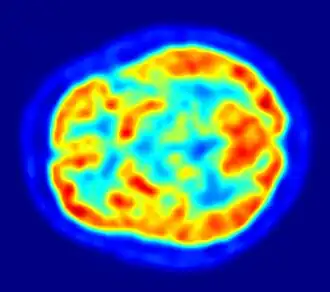

Этиология болезни Паркинсона на вторую половину 2011 года окончательно не выяснена. Этиологическими факторами риска считаются старение, генетическая предрасположенность, воздействие факторов окружающей среды[4][21][22]. Патоморфологически нормальное старение сопровождается уменьшением числа нейронов чёрной субстанции и наличием в них телец Леви. Старению также сопутствуют нейрохимические изменения в стриатуме — снижение содержания дофамина и фермента тирозингидроксилазы, а также уменьшение числа дофаминовых рецепторов. С помощью позитронно-эмиссионной томографии доказано, что темпы дегенерации нейронов чёрной субстанции при болезни Паркинсона намного выше, чем при нормальном старении[4].